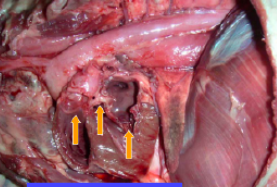

Hemopericardium

1 - pulmonary valve

2- aortia

3- mirtal valve

At ICS 3,4,5